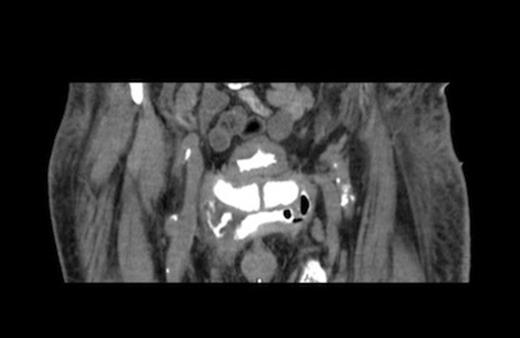

Radiographs confirmed subcutaneous gas associated with the swelling (figure 1). The patient was consented for incision and drainage of the collection, where it was noted that gas bubbles were released on initial stab incision. Copious grey watery fluid was drained from the cavity which appeared to track under the inguinal ligament. Cavity fluid and biopsy specimens were sent for microscopy, culture and sensitivity. The cavity was packed and broad spectrum antibiotics were started following consultation with a microbiologist. A pelvic CT scan with contrast was arranged (figure 2–4), which confirmed a vesicocutaneous fistula.

Figures 2, 3, and 4 are axial, sagittal, and coronal views, respectively, of computed tomography with contrast introduced by urinary catheter. This CT cystogram shows a leak/fistula at the low anterior bladder wall. The fistula has a communication with the pubic symphysis and a collection lies anterior to this. The tract extends distally, communicating with the cavity in the left anteromedial aspect of the thigh.